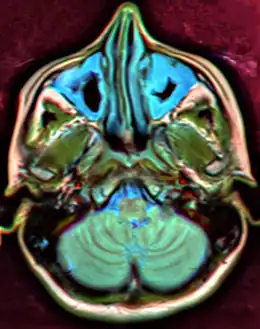

CT of chronic sinusitis

CT scan of chronic sinusitis, showing a filled right maxillary sinus with sclerotic thickened bone.

MRI image showing sinusitis. Edema and mucosal thickening appears in both maxillary sinuses.